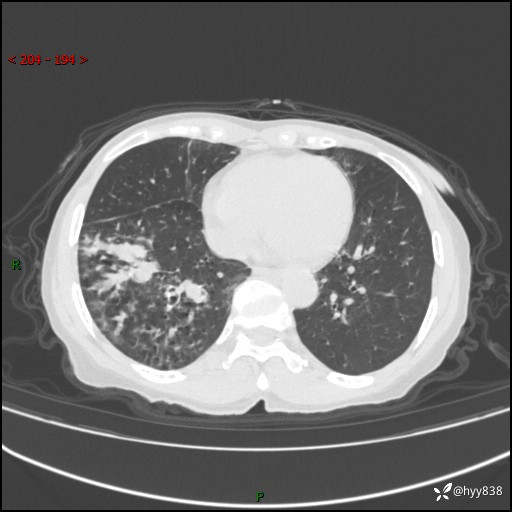

患者性别:男

患者年龄:69岁

简要病史:咳嗽咳痰2月,夜间加重

临床诊断:感染

胸部CT平扫